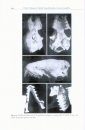

566 pages, 65 colour photos and colour illustrations, 333 b/w photos and b/w illustrations, 32 b/w distribution maps, tables

The Bats of Somalia and Neighbouring AreasThe Bats of Somalia and Neighbouring AreasThe Bats of Somalia and Neighbouring AreasThe Bats of Somalia and Neighbouring AreasThe Bats of Somalia and Neighbouring AreasThe Bats of Somalia and Neighbouring Areas